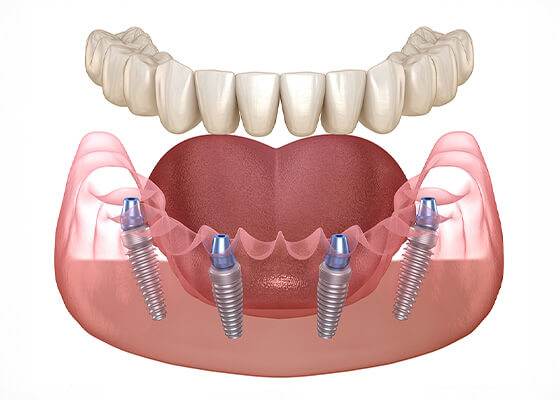

虫歯や歯周病でほとんどの歯が抜けてしまった患者さん。オールオン4治療で噛む力が回復し、美しい口元を取り戻したケース。

入れ歯が合わず、噛めない状態だった患者さん。オールオン4治療で、しっかり噛めるようになり、自然な見た目も獲得。

虫歯や歯周病で奥歯がほとんど抜けていた患者さん。オールオン4治療で、機能的にも審美的にも回復したケース。

入れ歯の「痛い」「噛めない」「外れる」「話しにくい」といった悩みは、インプラントやオールオン4で解消できます。

オールオン4は片顎198万円、インプラントは1本43万円。最大120回の分割払いも可能で、月々の負担を抑えて治療が受けられます。